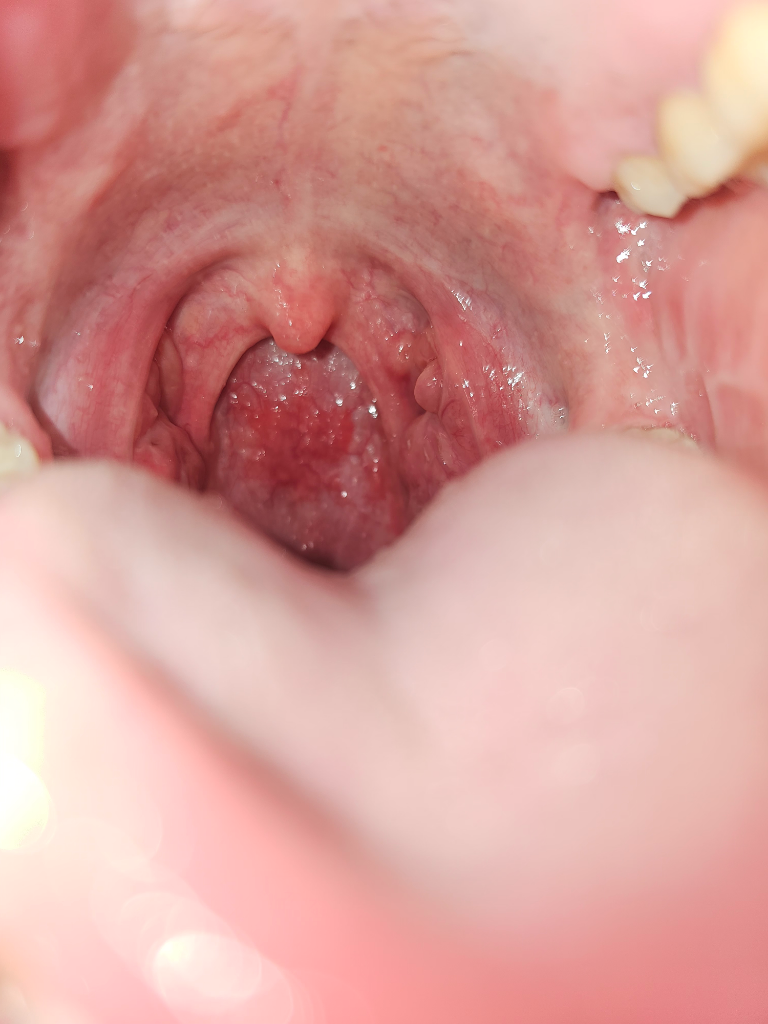

편도 위에 보이는 3개의 혹은 낭종인가요?

불과 몇년전에는 가장 안쪽에 혹만 생겼었는데 단순히 음주 및 스트레스로 생겨난 것으로 알고 있었습니다. 이번에도 술자리를 갖으면서 우연히도 그시기에 2개의 낭종(?) , 혹이 생겼더라구요 해서, 이빈후과에 가보니 뭐 별다른건 아니라고 대학병원가서 조직검사 받아보라고 하더군요.. 이게 뭔지 궁금합니다!

현재 목감기를 걸려있는 상태고 기침 가래 등으로 편도가 부었습니다 사진 오른쪽에 위치한 혹이 궁금합니다.

• 안녕하세요. 이송재 의사입니다. 사진으로 보았을때 양성 혹으로 보입니다. 추후에 편도 절제술 받으면서 함께 조직 검사를 받으면 좋을 것 같습니다.